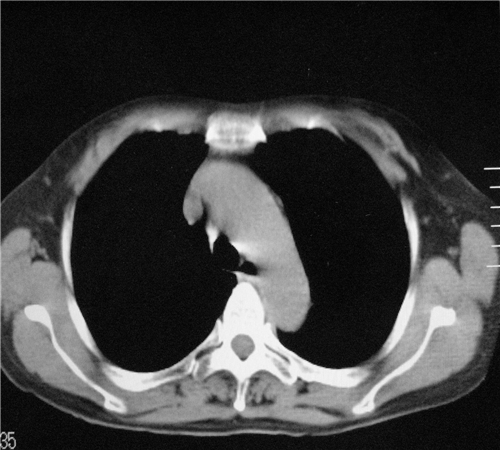

标题: CT26849:女67岁反复胸痛两天余,临床考虑夹层。 [打印本页]

标题: CT26849:女67岁反复胸痛两天余,临床考虑夹层。

右肺感染,未见夹层。

未见夹层

既然考虑夹层,建议强化!另:右下肺感染!

1)右肺感染性病变。2)建议行ct增强扫描或mri检查排除主动脉夹层。

双下肺感染,右侧显著。有无夹层,增强扫描后再诊断。

1. 感染性病变,2.未见夹层,3.食道未见异常。